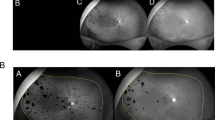

Quantification of retinal hemorrhagic patterns at the posterior pole of eyes with acute branch retinal vein occlusion using the parallelism method.

Images of the posterior pole of an eye with a typical flame-shaped retinal hemorrhage (A–D) and of an eye with a non-flame-shaped blot retinal hemorrhage (E–H) are shown. Optos color fundus photographs (A,E), the split green channel of the originals (B,F), extracted skeletonized images of the retinal hemorrhage (C,G) and hemorrhage-sparse areas (D,H) are shown. The skeletonized images are made by applying a filter using ImageJ software followed by binarization with Otsu’s thresholding method. The parallelism values are then calculated based on the processed images. Parallelism is expected to show higher values in eyes with a flame-shaped retinal hemorrhage and lower values in eyes with a non-flame-shaped dot or blot retinal hemorrhage. The averaged parallelism values are 0.496 [(0.590 + 0.402)/2] in an eye with a flame-shaped retinal hemorrhage (C,D) and 0.084 [(0.062 + 0.106)/2)] in an eye with a non-flame-shaped blot retinal hemorrhage (G,H).